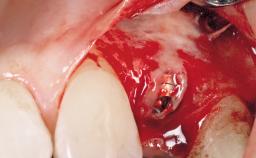

Immediate Flapless Placement of an Implant in a Maxillary Left Central Incisor Site

| Placement Protocol | Immediate implant placement |

| Socket Morphology | Single-root socket |

| Socket Integrity | Damage to one or more bone walls |

| Bone Volume | Damage to one or more socket walls |